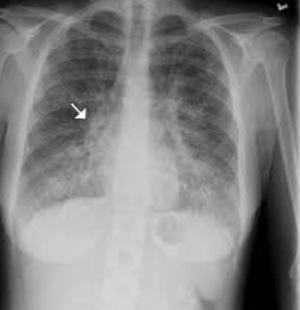

Pulmonary cancer first stade